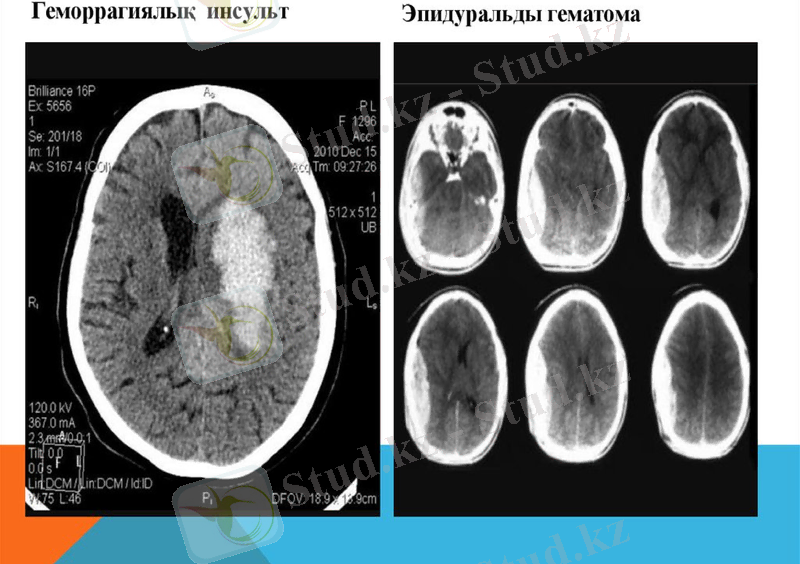

аппараттық зерттеулер:

компьютерлік немесе магниттік-резонанстық томография, ЭЭГ (электроэнцефалография), нейромиография, рентгенография, УДЗ, допплерография, ЭКГ;